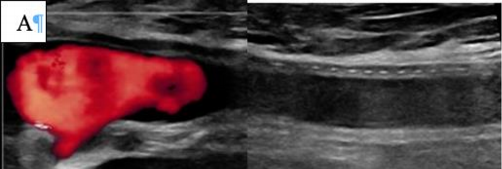

Рекомендуется проводить пункцию под ультразвуковым контролем с целью точного прокола передней стенки артерии и минимизации риска повреждения задней стенки [185, 186].

Комментарий: Анализ пяти РКИ показал, что пункция артерии под УЗ-контролем снижает частоту осложнений по сравнению с пункцией по анатомическим ориентирам [180]. Использование УЗИ уменьшало число попыток пункции (ОШ 0,24), риск прокола вены (ОШ 0,18) и кровотечений (ОШ 0,41). Сравнительных данных об эффективности антеградного и ретроградного доступа при тромболизисе нет. Антеградный доступ через ОБА упрощает реканализацию тромбозов дистальных артерий, а через артерии верхней конечности – прохождение через тромбированную бифуркацию аорты. Ретроградный контралатеральный доступ через ОБА наиболее распространён, обеспечивает стабильное положение катетера и снижает риск смещения и кровотечения [181]. Этот доступ также позволяет избежать необходимости сдавления ОБА ишемизированной нижней конечности при гемостазе, после удаления набора для чрескожного сосудистого доступа (интродьюсер) из места пункции.